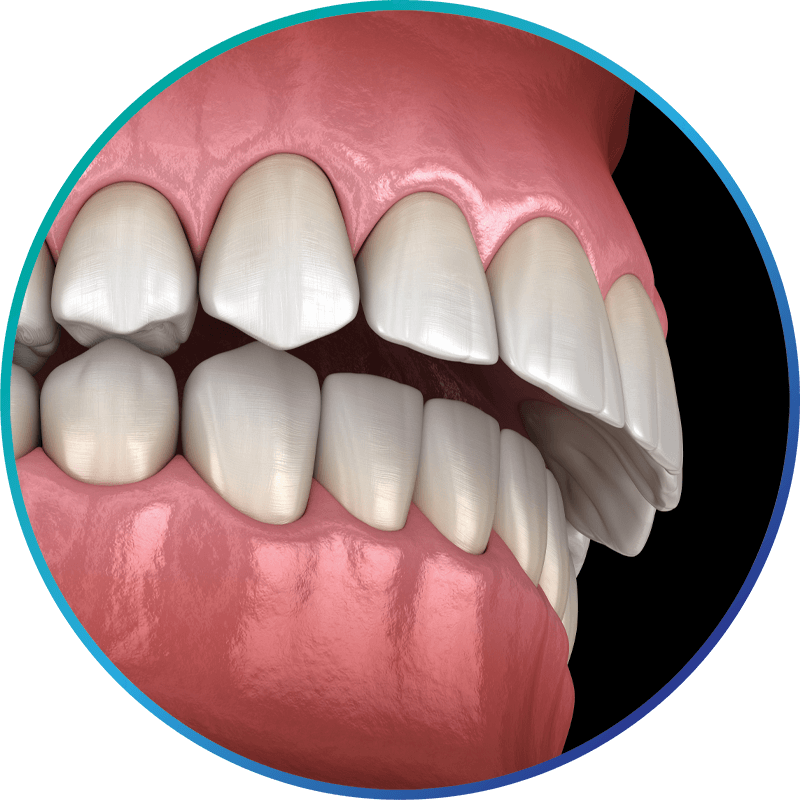

Jaw misalignment—when your top and bottom rows of teeth don’t fit together as you bite down—can cause you a host of problems, including headaches, facial pain, and ringing in the ears. In the most severe instances, it can create difficulties in eating, speaking, breathing, and sleeping. On top of this, facial asymmetry can compromise your facial esthetics. Your face may be noticeably uneven, making you feel self-conscious about your appearance.

While jaw misalignment can sometimes be alleviated by the use of a mouthguard or through orthodontia, severe misalignment may require surgery. Whether your jaws are out of alignment or your facial features are uneven, the skilled, experienced oral surgery team here can correct those issues and allow you to enjoy a more comfortable and self-confident life. As medical doctors and surgeons we’re qualified to effectively treat complex and even medically compromised cases through jaw surgery.